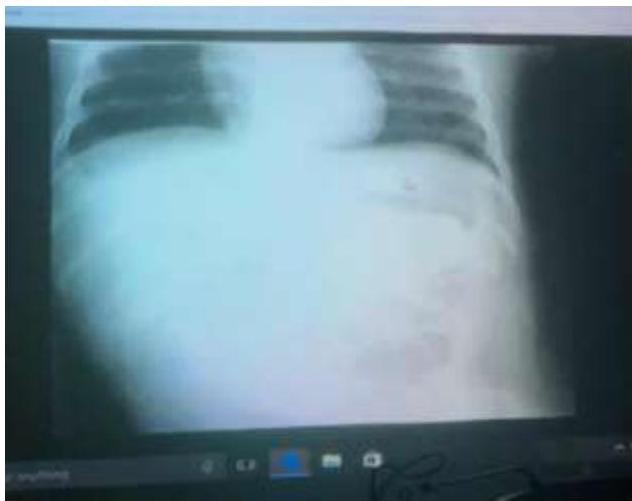

Heart Failure with Pulmonary Edema:

Scenario: 3-month-old with heart failure, cyanotic and cardiac murmur

Findings:

- Small heart

- Pulmonary edema

Preterm Infant with Respiratory Distress

- Preterm 29 weeks gestation C/S delivery showed severe respiratory distress soon after birth - RDS

- Air bronchograms

-

There is a homogeneous opacification of both lungs with white-out lungs - (1 .field (grounds glass appearance) and air bronchogram bilaterally

.The diagnosis is Acute Respiratory Distress Syndrome (ARDS) - (2